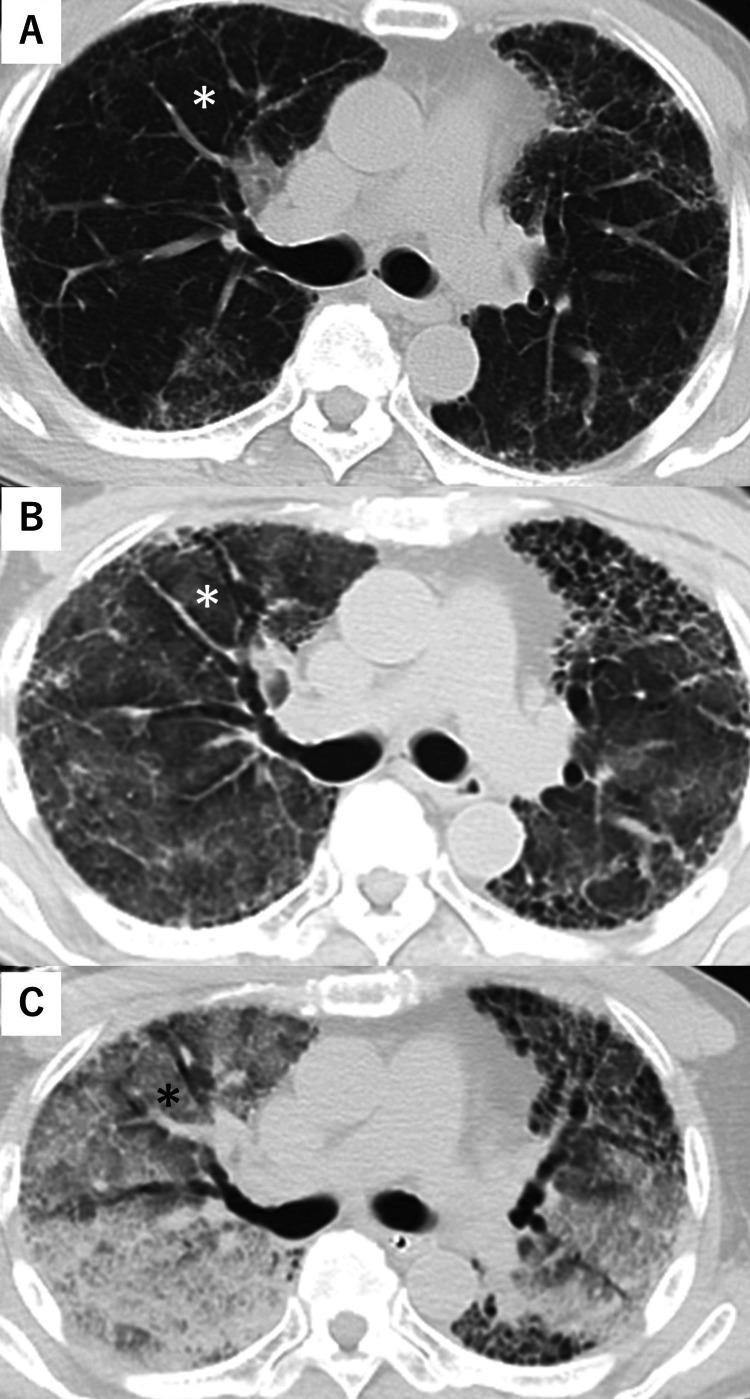

A 72-year-old man with idiopathic pulmonary fibrosis (IPF) was on home oxygen therapy at 1 L/min. He fell approximately 3 m onto a concrete surface while painting the roof of his home and was emergently transported to a local hospital due to pain in his lower back and right lower limb. His initial Krebs von den Lungen level decreased with medical treatments but has shown an increasing trend over the past three respiratory outpatient visits. His other medical conditions, including dyslipidemia, lumbar pain, and allergic rhinitis, were treated with several drugs prescribed by a nearby clinic. At the previous hospital, an increased oxygen demand of around 5 L via mask was noted, although other vital signs were stable. A plain whole-body computed tomography (CT) scan revealed pulmonary edema, a fracture of the right femoral neck, and a fracture of the third lumbar vertebral body. During transfer to our hospital for surgery, crossing the Amagi Pass at an elevation of approximately 830 m, the patient's respiratory condition rapidly deteriorated. Upon arrival, the cardiac wall movement was hyperdynamic, and PaO was 29 mmHg under supplemental oxygen at 15 L/min, necessitating oral endotracheal intubation and initiation of mechanical ventilation. A chest CT scan showed worsening diffuse ground-glass opacities in both lungs compared to the previous CT scan at the referring hospital. Despite positive pressure ventilation with the mechanical ventilator, the patient's condition did not improve, and he died in the emergency room. Acute respiratory distress syndrome (ARDS) can occur following severe trauma but the onset of ARDS due to moderate trauma is extremely rare. Considering the possibility of an acute exacerbation of IPF prior to the injury, this report discusses the possibility of developing ARDS due to trauma-induced cytokines and lung damage from damage-associated molecular patterns, the possibility of inhaling dust while working on the roof, pneumonia caused by prescribed medication, viral infections, exposure to pollen and/or high altitude while passing through the mountain pass, and hypoxemia-inducing pulmonary edema.

一名72岁的特发性肺纤维化(IPF)男性患者正在家中接受1升/分钟的氧气治疗。他在家中粉刷屋顶时从约3米高处跌落到水泥地面,因下背部和右下肢疼痛被紧急送往当地医院。他最初的克雷布斯·冯·登·伦根水平经药物治疗后有所下降,但在过去三次呼吸门诊就诊时呈上升趋势。他的其他疾病,包括血脂异常、腰痛和过敏性鼻炎,由附近诊所开的几种药物进行治疗。在前一家医院,虽然其他生命体征稳定,但通过面罩吸氧需求增加至约5升。全身普通计算机断层扫描(CT)显示肺水肿、右股骨颈骨折和第三腰椎椎体骨折。在转往我院进行手术途中,经过海拔约830米的天城山口时,患者的呼吸状况迅速恶化。到达时,心脏壁运动亢进,在15升/分钟的补充氧气下,动脉血氧分压(PaO)为29毫米汞柱,需要进行气管插管并开始机械通气。胸部CT扫描显示,与转诊医院之前的CT扫描相比,双肺弥漫性磨玻璃影加重。尽管使用机械通气进行正压通气,但患者病情并未改善,最终在急诊室死亡。急性呼吸窘迫综合征(ARDS)可发生在严重创伤后,但中度创伤导致ARDS的情况极为罕见。考虑到受伤前IPF急性加重的可能性,本报告讨论了因创伤诱导的细胞因子和损伤相关分子模式导致的肺损伤而发生ARDS的可能性、在屋顶工作时吸入灰尘的可能性、处方药引起的肺炎、病毒感染、在通过山口时接触花粉和/或高海拔以及低氧血症诱导的肺水肿。